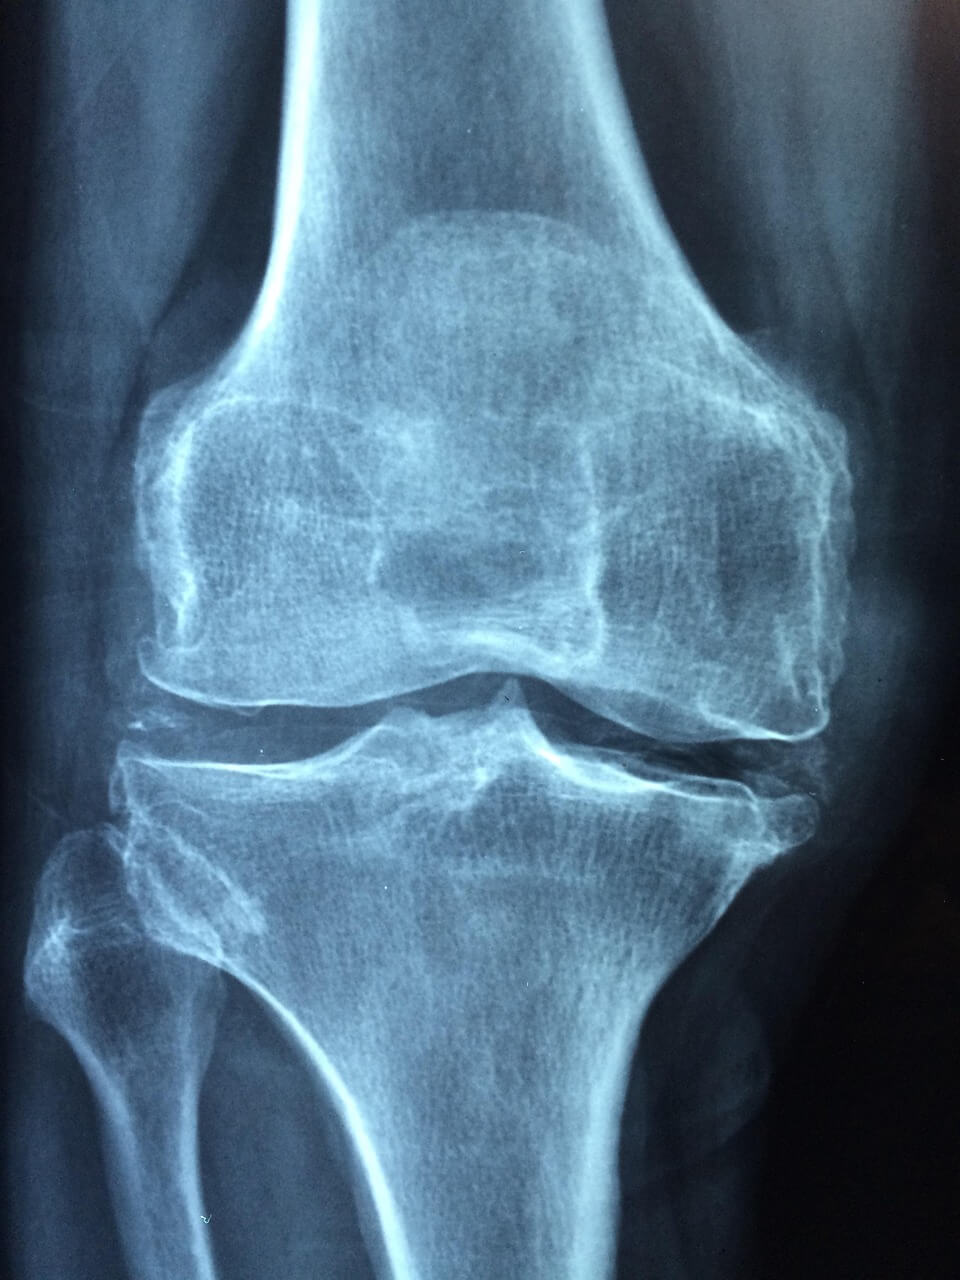

언제 병원에 가야 할까요?

- 통증이 2주 이상 계속되거나 점점 심해질 때.

- 무릎이 붓고 열감이 있으며 밤에도 통증이 계속될 때.

- 걷기나 체중부하 시 무릎이 흔들리거나 불안정할 때.

초기 진단이 빠를수록 비수술적 치료로 호전될 확률이 높습니다. 지금 바로 정형외과에서 진단받아보세요.